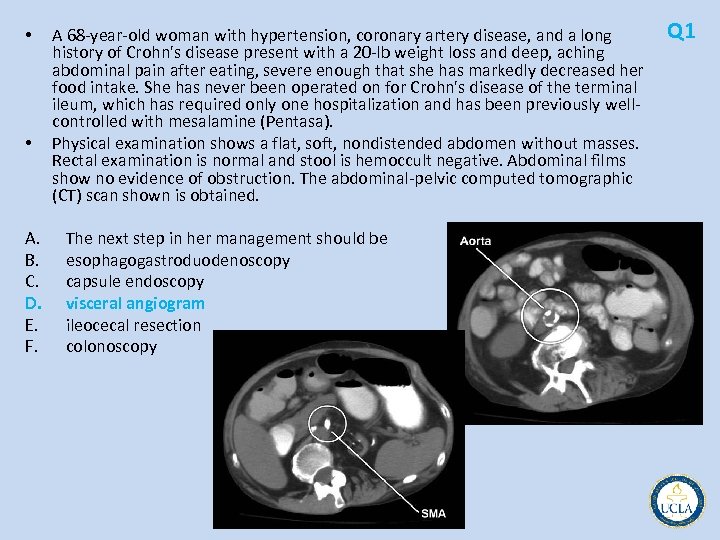

Q 1